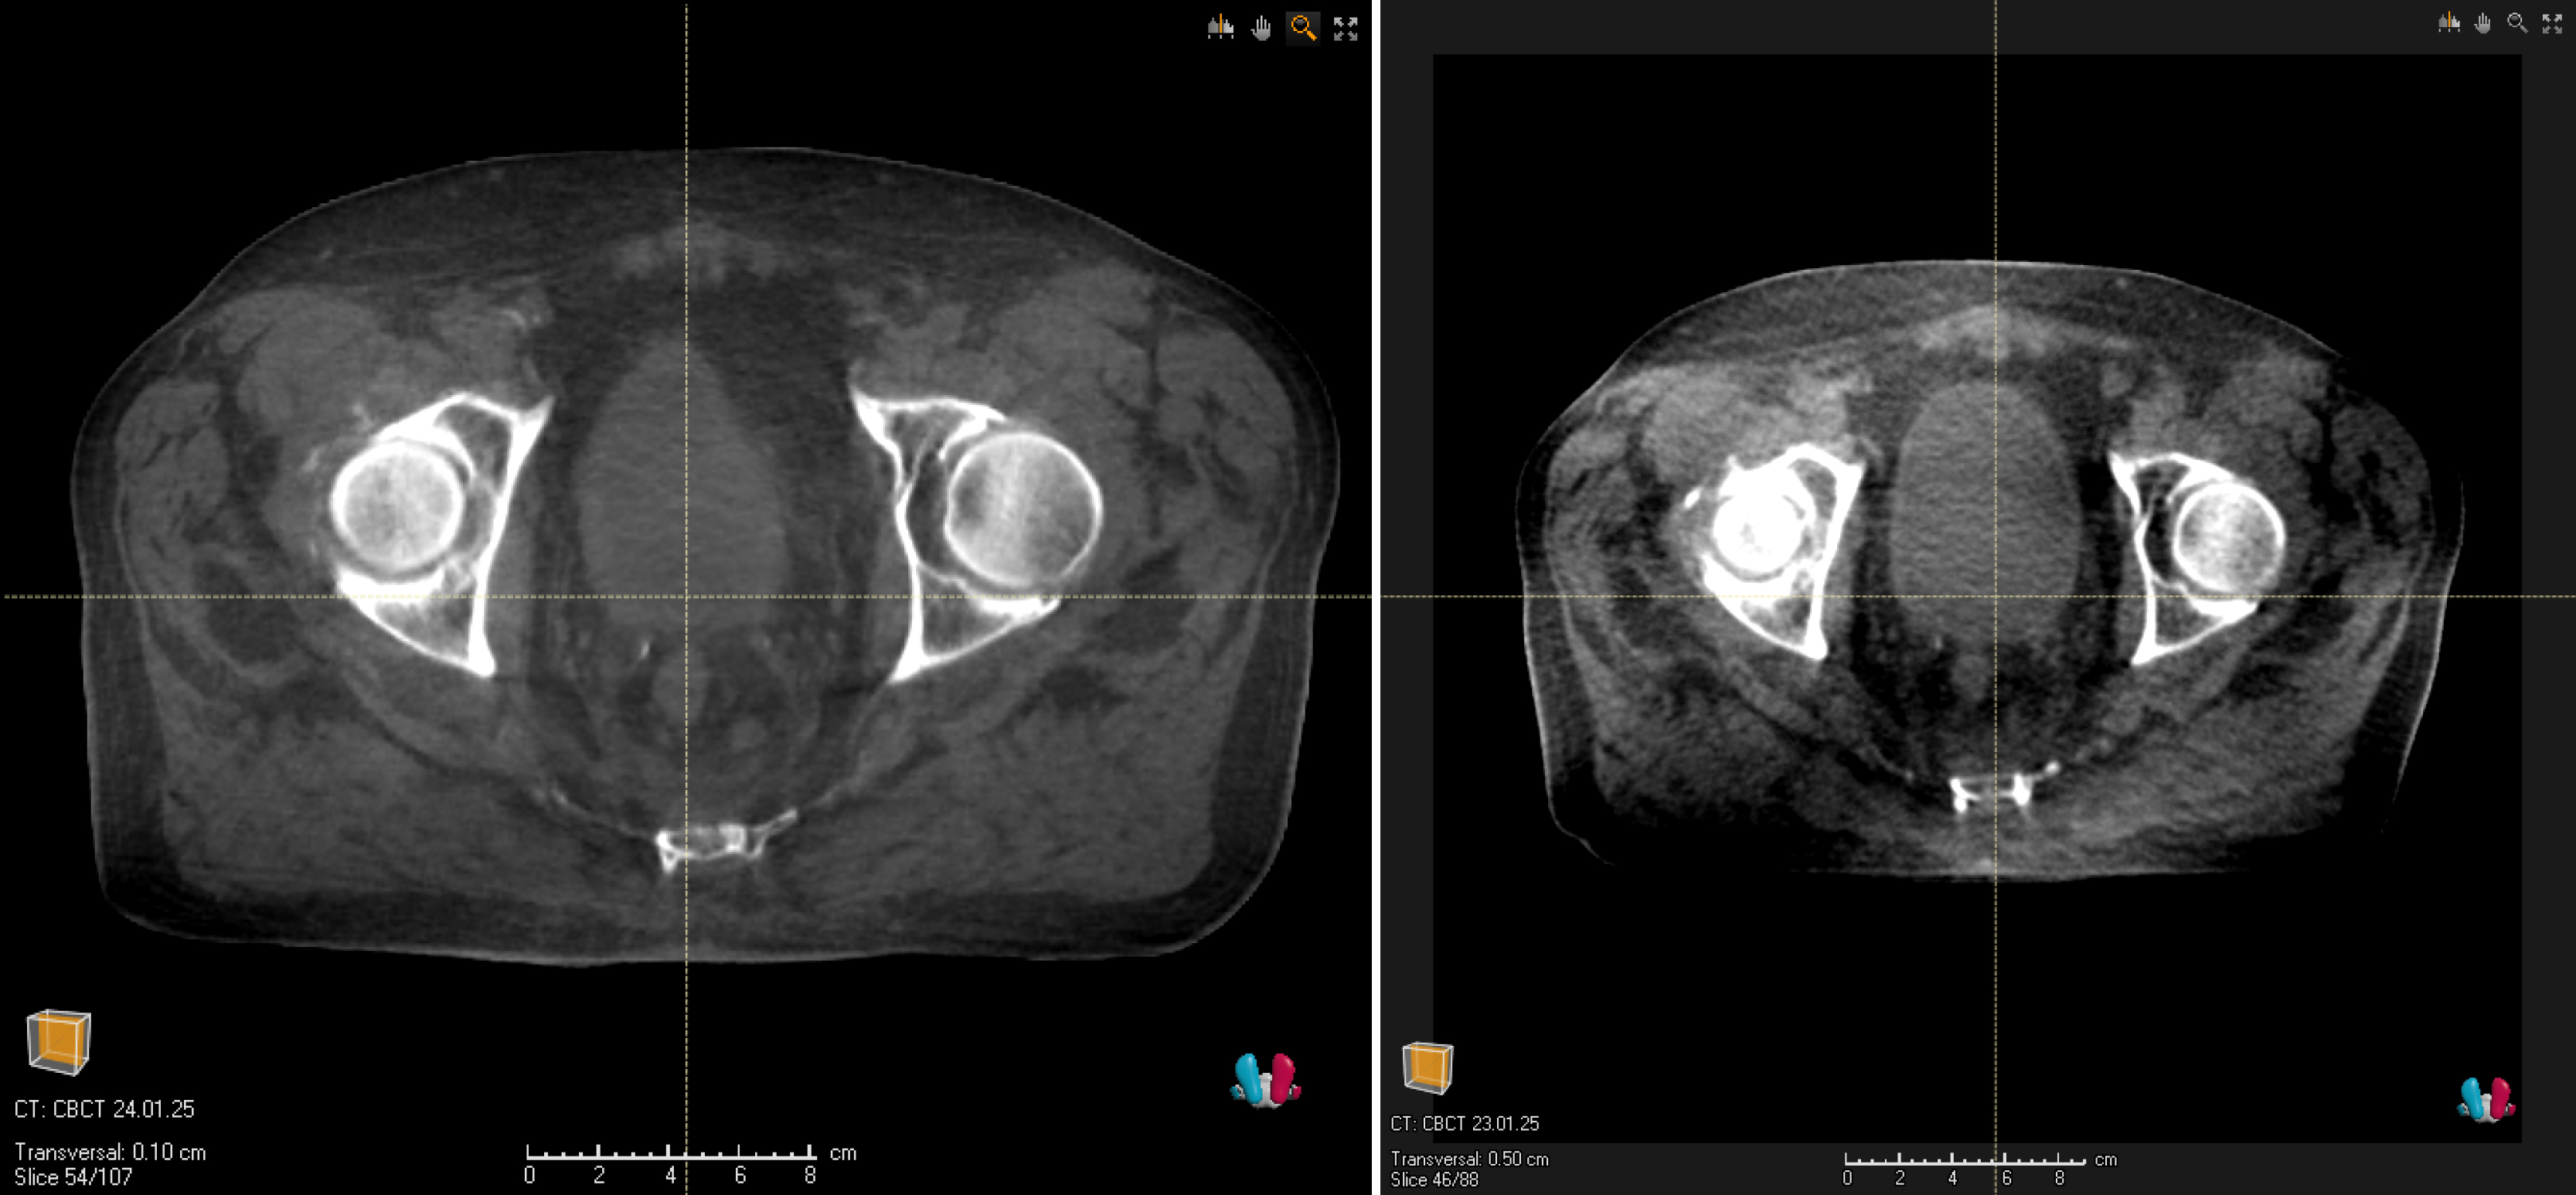

Die Klinik und Poliklinik für Strahlentherapie und Radioonkologie am Universitätsklinikum Carl Gustav Carus in Dresden ist die weltweit erste Einrichtung, die Patientinnen und Patienten auf dem Versa HD Linac von Elekta mit der neuen hochauflösenden KI-gestützten Bildgebungslösung Iris behandelt. Diese ermöglicht es den Medizinerinnen und Medizinern, Zielvolumen und kritische Strukturen für jede Fraktion mit noch besseren und detaillierteren Bildern zu visualisieren. Ende Januar wurde der erste Patient mit diesem innovativen Verfahren behandelt.

„Wir stellen eine deutlich verbesserte Bildqualität fest, welche die bildgeführte Einstellung der Patientinnen und Patienten vereinfacht und die Bestrahlung qualitative verbessert“, sagt Prof. Esther Troost, Radioonkologin und Direktorin der Klinik und Poliklinik für Strahlentherapie und Radioonkologie. „Die Hochschulmedizin Dresden setzt in der Onkologie immer wieder neue Maßstäbe. Das enge Zusammenwirken von Forschung und Patientenversorgung in Zusammenarbeit mit der Industrie ermöglicht es uns stetig, Diagnostik und Therapie zu verbessern“, sagt Prof. Uwe Platzbecker, Medizinischer Vorstand am Universitätsklinikum Dresden.

Iris bietet dem Strahlentherapie-Team eine hochauflösende, KI-gestützte Bildgebung, einen radikal verbesserten Kontrast zur Visualisierung der Zielgrenzen und des benachbarten gesunden Gewebes. Das ist wichtig, um die Strahlendosis genau zu bestimmen und so präzise wie möglich, das erkrankte Gewebe zu bestrahlen. So können Nebenwirkungen sowie Risiken für das umliegende Gewebe minimiert werden. „Diese neue Technik bietet eine Voraussetzung für die Reduktion von Nebenwirkungen der Strahlentherapie, wenn intensive Behandlungsschemata appliziert werden“, ergänzt Prof. Mechthild Krause, Direktorin der Klinik für Strahlentherapie und Radioonkologie und des OncoRay – Nationales Zentrum für Strahlenforschung in der Onkologie, einem Forschungszentrum des Universitätsklinikum Carl Gustav Carus, der Medizinischen Fakultät an der Technischen Universität Dresden und dem Helmholtz-Zentrum Dresden-Rossendorf. „Wir freuen uns sehr, dass wir mit Iris die personalisierten Behandlungsmöglichkeiten auf mehr Patientinnen und Patienten sowie Kliniken ausweiten können“, sagt der Elekta-Projektleiter. „Das Technologie-Upgrade, das die Bildqualität erheblich verbessert, kann einfach und mit minimaler Störung installiert werden, wie das Team am Universitätsklinikum Carl Gustav Carus bewiesen hat.“ „Es ehrt uns sehr, dass wir die erste Klinik weltweit sind, die diese innovative Bildgebungslösung auf einem Versa HD einsetzt und freuen uns auf die weitere Zusammenarbeit“, sagt Stefan Pieck, administrativer Direktor des OncoRay.